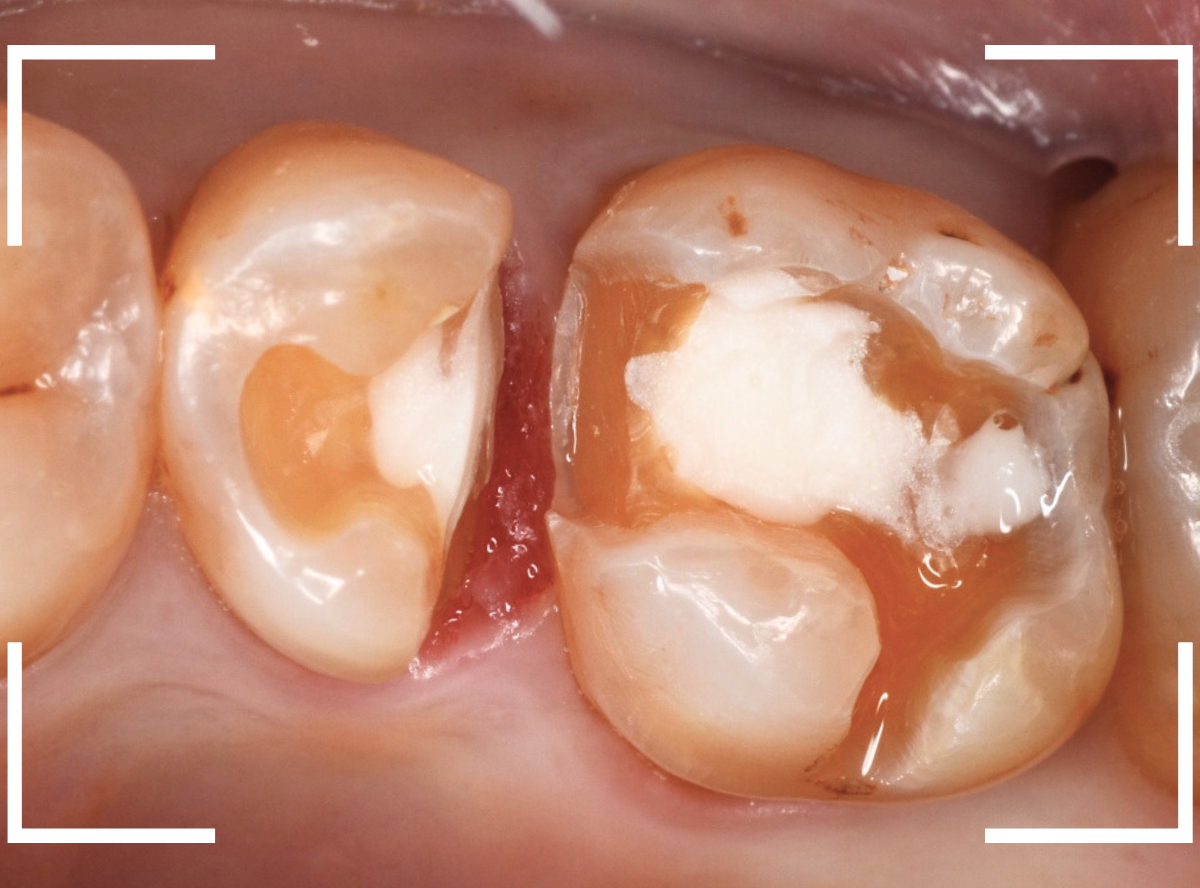

Case.10 虫歯治療と審美修復

今回は、メタルインレーの手前の歯が虫歯になってしまった患者さんのケースです。

「虫歯の治療の際に、後ろのメタルインレーも白くしたい」とのご希望で、一緒に治療する事になりました。

レントゲン写真で確認します。

メタル・インレーの中は問題なさそうです。

まず、メタル・インレーを除去します。

やはりメタル・インレーの中は問題なさそうですね。

手前の虫歯を除去したところです。

両歯とも、白い歯を希望されましたので、手前をE-MAXインレー、奥歯をジルコニア・インレーで治療する事になりました。